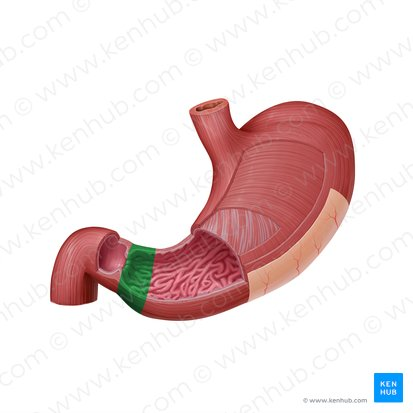

Pyloric sphincter

A muscular ring located at the junction of the stomach and the duodenum (the first part of the small intestine) that controls the emptying of stomach contents into the duodenum.

Pyloric canal

the narrow passageway that leads from the pyloric antrum to the pyloric sphincter.

Pyloric antrum

The funnel-shaped region of the stomach that precedes the pyloric canal.

Pylorus

The distal, narrow region of the stomach that connects to the duodenum, including the pyloric antrum, pyloric canal, and pyloric sphincter.